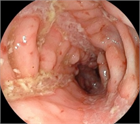

1. クローン病とは、原因不明の、口腔内から肛門周囲までの腸管のどの部位にでも発症する炎症性腸疾患の1つである。